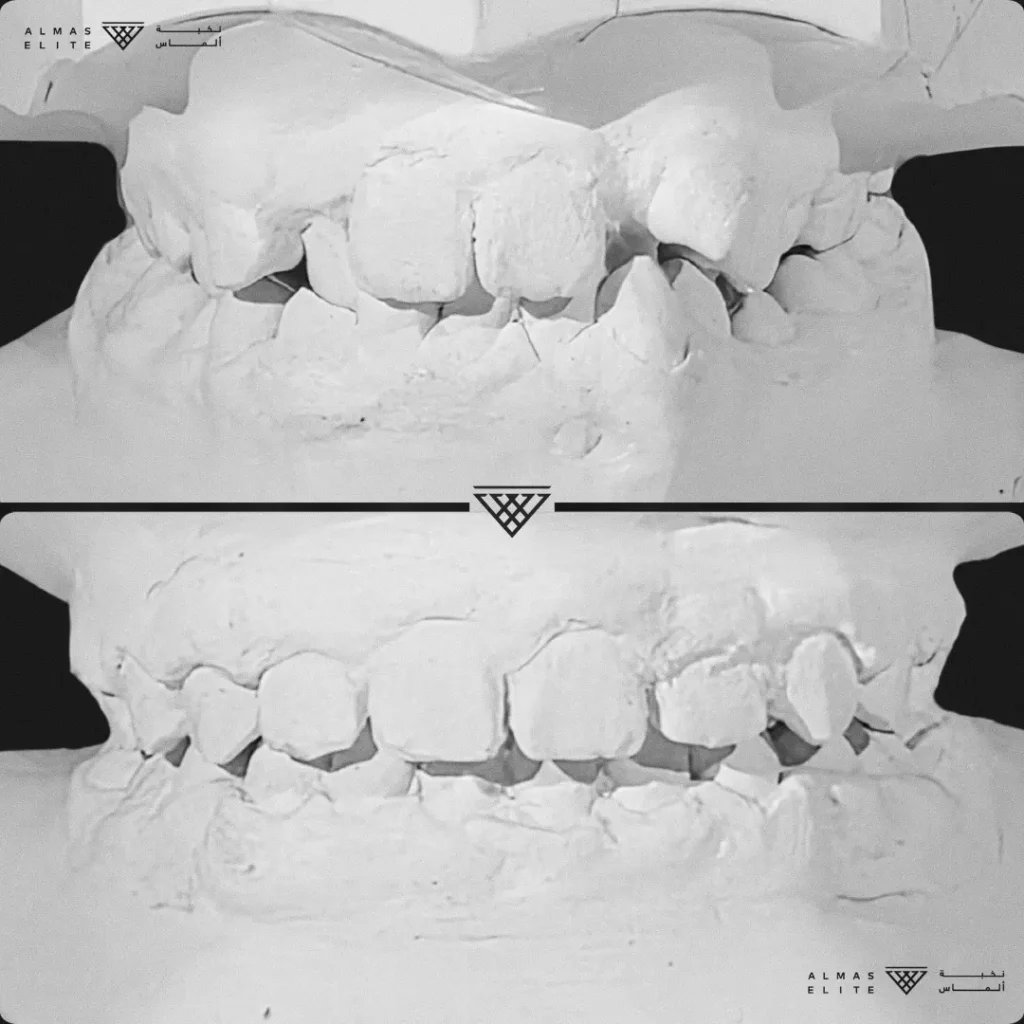

٢) التقييم والتشخيص الشامل

يشمل صور الأشعة والتحليل الرقمي للأسنان والفكين للوصول إلى تشخيص دقيق.

٣) وضع خطة علاجية مخصصة

تتضمن نوع الجهاز الأنسب، المدة المتوقعة، وتكلفة العلاج، مع شرح واضح لما يمكن توقعه أثناء رحلة التقويم.

٤) التركيب والمتابعة

يتم تركيب الجهاز والمتابعة بزيارات دورية غالبًا كل 3–6 أسابيع حسب الخطة العلاجية.